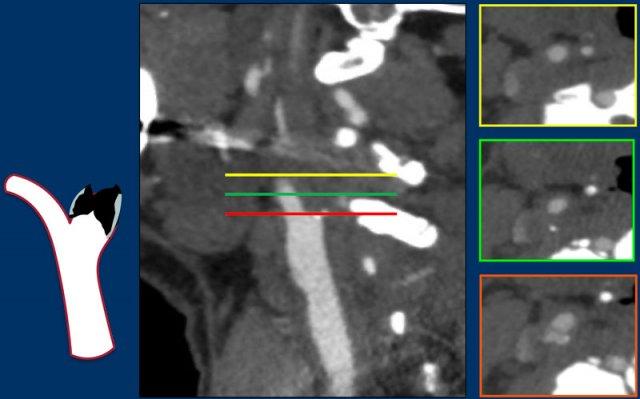

Gần tắc hoàn toàn

Trong trường hợp hẹp nặng hoặc gần tắc hoàn toàn, đường kính của ACI ở đoạn trên vị trí hẹp bị thu nhỏ và nhỏ hơn so với ICA bên đối diện cũng như ECA cùng bên.

Trong trường hợp tắc hoàn toàn, hình ảnh thuốc cản quang có dạng hình { hoặc dấu ngoặc nhọn, khác với hình ảnh tắc trong bóc tách động mạch hoặc giả tắc.

Gần tắc hoàn toàn (2)

Trong trường hợp này, động mạch cảnh chung có đường kính bình thường (hình 1).

Có hẹp nặng với mảng xơ vữa vôi hóa một phần tại vị trí xoang cảnh (2).

ICA ở đoạn trên vị trí hẹp có khẩu kính nhỏ (3). Xem thêm mũi tên trên ảnh tái tạo mặt phẳng đứng dọc.

Các tiêu chí chẩn đoán gần tắc hoàn toàn bao gồm:

- Khẩu kính ICA đoạn xa nhỏ hơn so với ICA bên đối diện (hình 3).

- Khẩu kính ICA đoạn xa nhỏ hơn so với động mạch cảnh ngoài (ECA) cùng bên (hình 3).

Vận tốc đỉnh tâm thu trên siêu âm Doppler thường tăng tương ứng với mức độ hẹp, tuy nhiên trong trường hợp gần tắc hoàn toàn, vận tốc đỉnh tâm thu sẽ giảm xuống mức rất thấp như trong trường hợp này (20 cm/giây).

Lưu ý mảng vôi hóa tại vị trí xoang cảnh và khẩu kính nhỏ của ICA đoạn xa, nhỏ hơn so với khẩu kính của ECA.